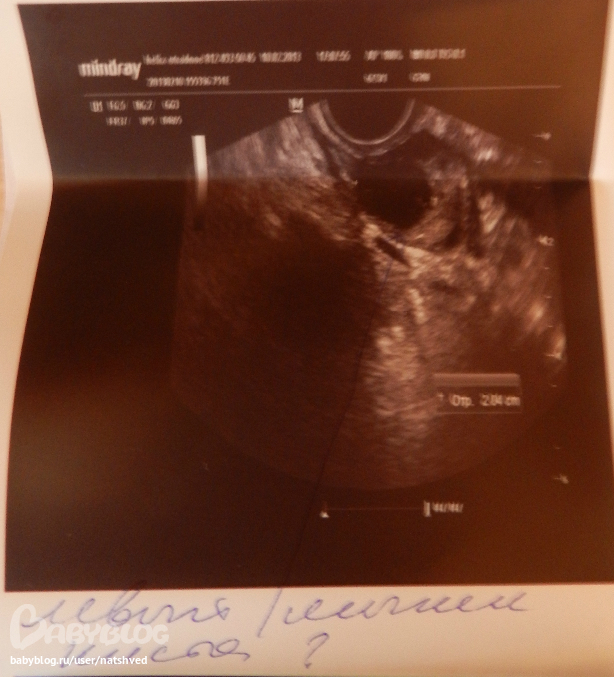

ЛЯ киста ЖТ 20мм - пипец! в жизни не было кисты, откуда она??? ДФ 11мм